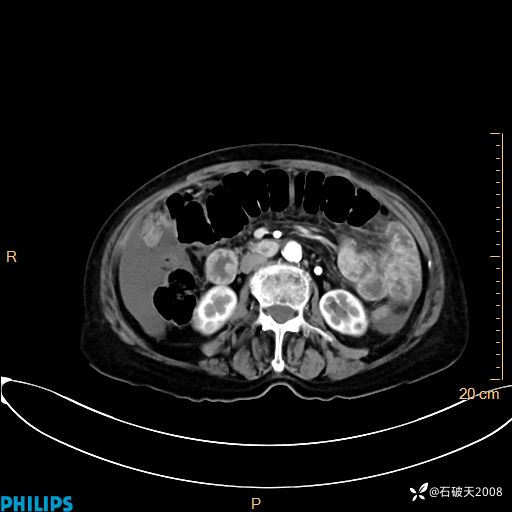

MIP